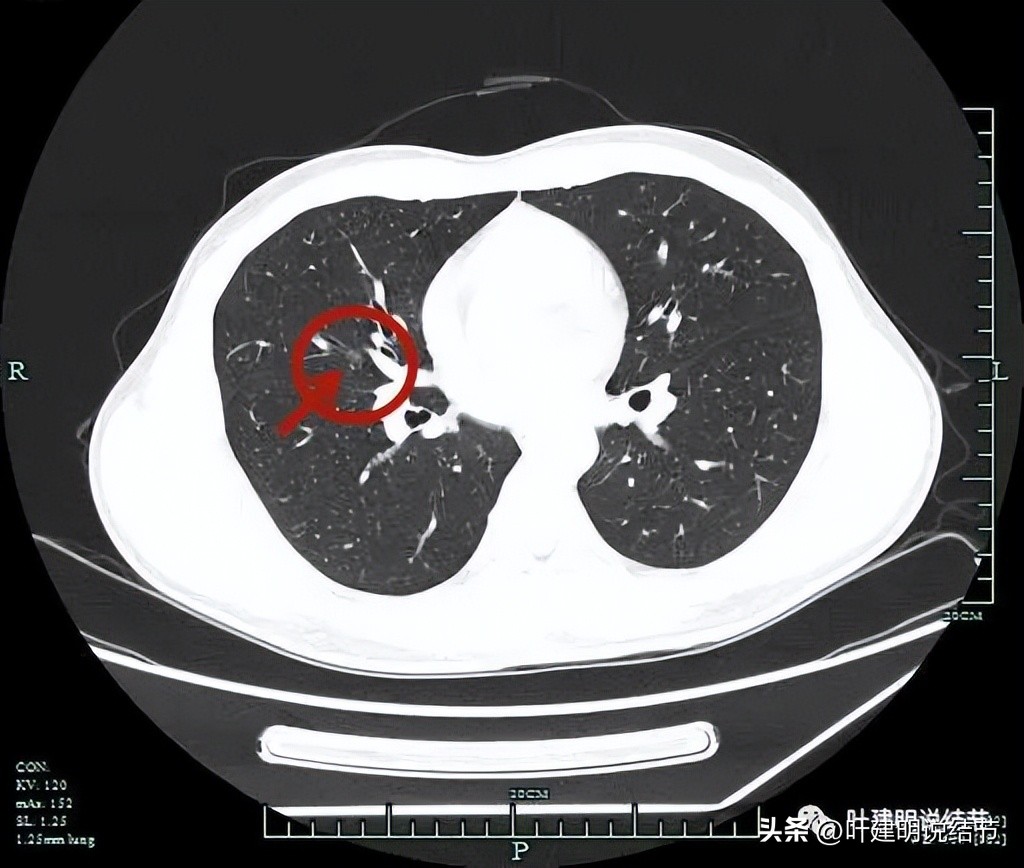

薄层平扫见三处病灶:

病灶2:右中叶靠近肺门部,外侧段支气管壁紧邻处磨玻璃结节,感觉轮廓也较清,边缘不太光滑,考虑恶性范畴的可能性大些。